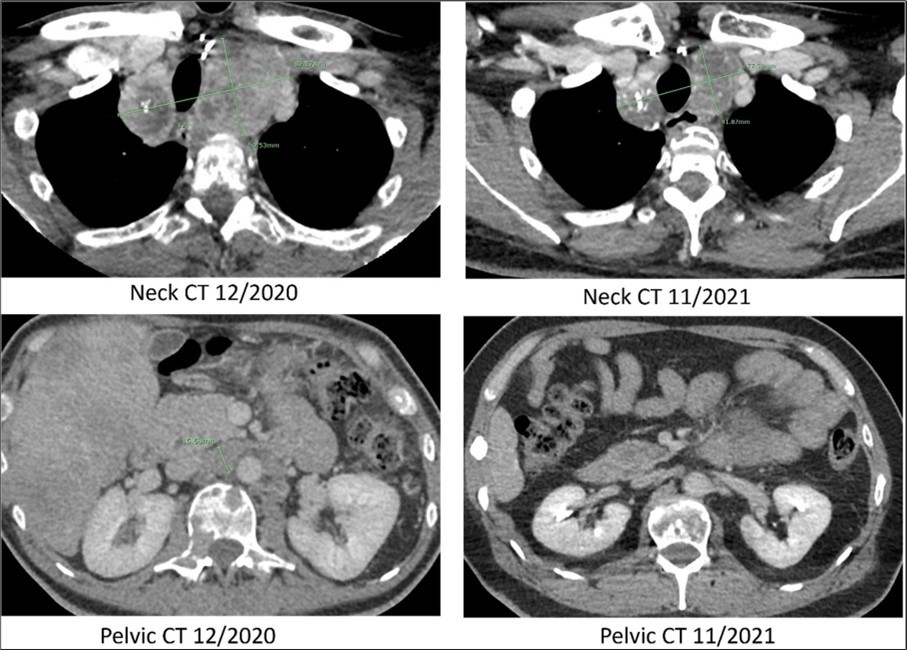

The patient presented to radiation oncology in September 2020 with severe back pain and shown to have widely metastatic disease with a calcitonin level >40,000 pg/mL and carcinoembryonic antigen (CEA) level >2,500 ng/mL. Computerized tomography (CT) with contrast of the chest, abdomen and pelvis revealed worsening mediastinal lymphadenopathy with progressive mass effect and rightward deviation of the trachea at the superior mediastinum (Figure 2). Patient received radiotherapy for four weeks causing epiglottitis and subsequent 25lb weight loss. Progressive osseous metastatic disease was identified with innumerable new expansile lytic lesions throughout the vertebral bodies, posterior elements, ribs, sternum, and scapulae, resulting in pathologic fractures of the C7, T4, T6, and T12 vertebral bodies as well as right posterior 10th rib. In addition, there were innumerable new and enlarging liver lesions and bilateral pulmonary nodules. Patient declined further therapy including further imaging studies.

Figure 2.Computed tomography. CT scans of the neck and pelvis with contrast in December of 2020 (prior to Pralsetinib) and in November of 2021 (eleven months after the start of Pralsetinib). The 2020 neck CT showed a large mass at the thoracic inlet measuring 89mm x 50mm. In 2021 this same mass post treatment had decreased in size to 77mm x 41mm. The 2020 pelvic CT showed a retroperitoneal lymph node enlargement to 15mm, which resolved on the 2021 scan.

The patient was re-referred to the Mays Cancer Center/UTHSA in November of 2020. The patient reported significant mobility issues and severe pain, rating a 3 on the Eastern Cooperative Oncology Group Performance Status (ECOG PS). Circulating tumor DNA (ctDNA) analysis (Guardant360) identified a RET 898-901Del and reported as a variant of unknown significance. Since the deletion was in the activation loop of RET kinase, the treating physician considered that the mutation was constitutively activating RET kinase. The patient was treated with Pralsetinib a small molecule inhibitor targeting the ATP-binding site of the RET kinase in December 2020 with a starting dose of 100mg per day with dose escalation every week to 400mg by mouth (PO) daily (QD). In January 2021 the patient noticed an improvement in quality of life (ECOG PS improved 2) with a significant decrease in serum calcitonin and CEA levels and decreased tumor size. The 400 mg PO QD dosing lead a decrease in platelet count to 51 K/mL in mid-February 2021. Pralsetinib was withheld for five weeks to allow for platelet recovery. In the interim the serum calcitonin level increased with disease progression. The patient was restarted at 200mg of Pralsetinib PO QD in March 2021 which was better tolerated with no further symptoms or signs of toxicity. The Pralsetinib treatment improved the patient’s mobility, pain, and over all quality of life, rating a 0 on the ECOG PS by September 2021.